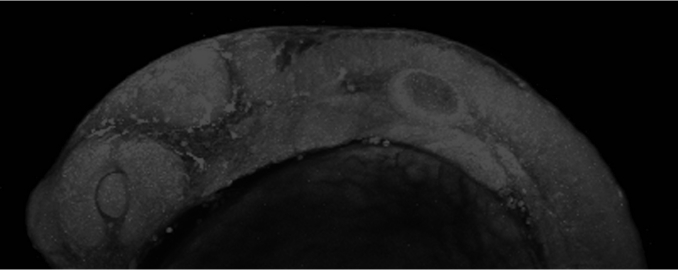

The carotid artery of a mouse with artherosclerosis

The carotid artery of a mouse with atherosclerosis. Red, yellow, and green immune cells take up cholesterol and help regulate inflammation in the arterial wall (blue). Photo by Sara McArdle, La Jolla Institute for Immunology, LJI Microscopy Core.